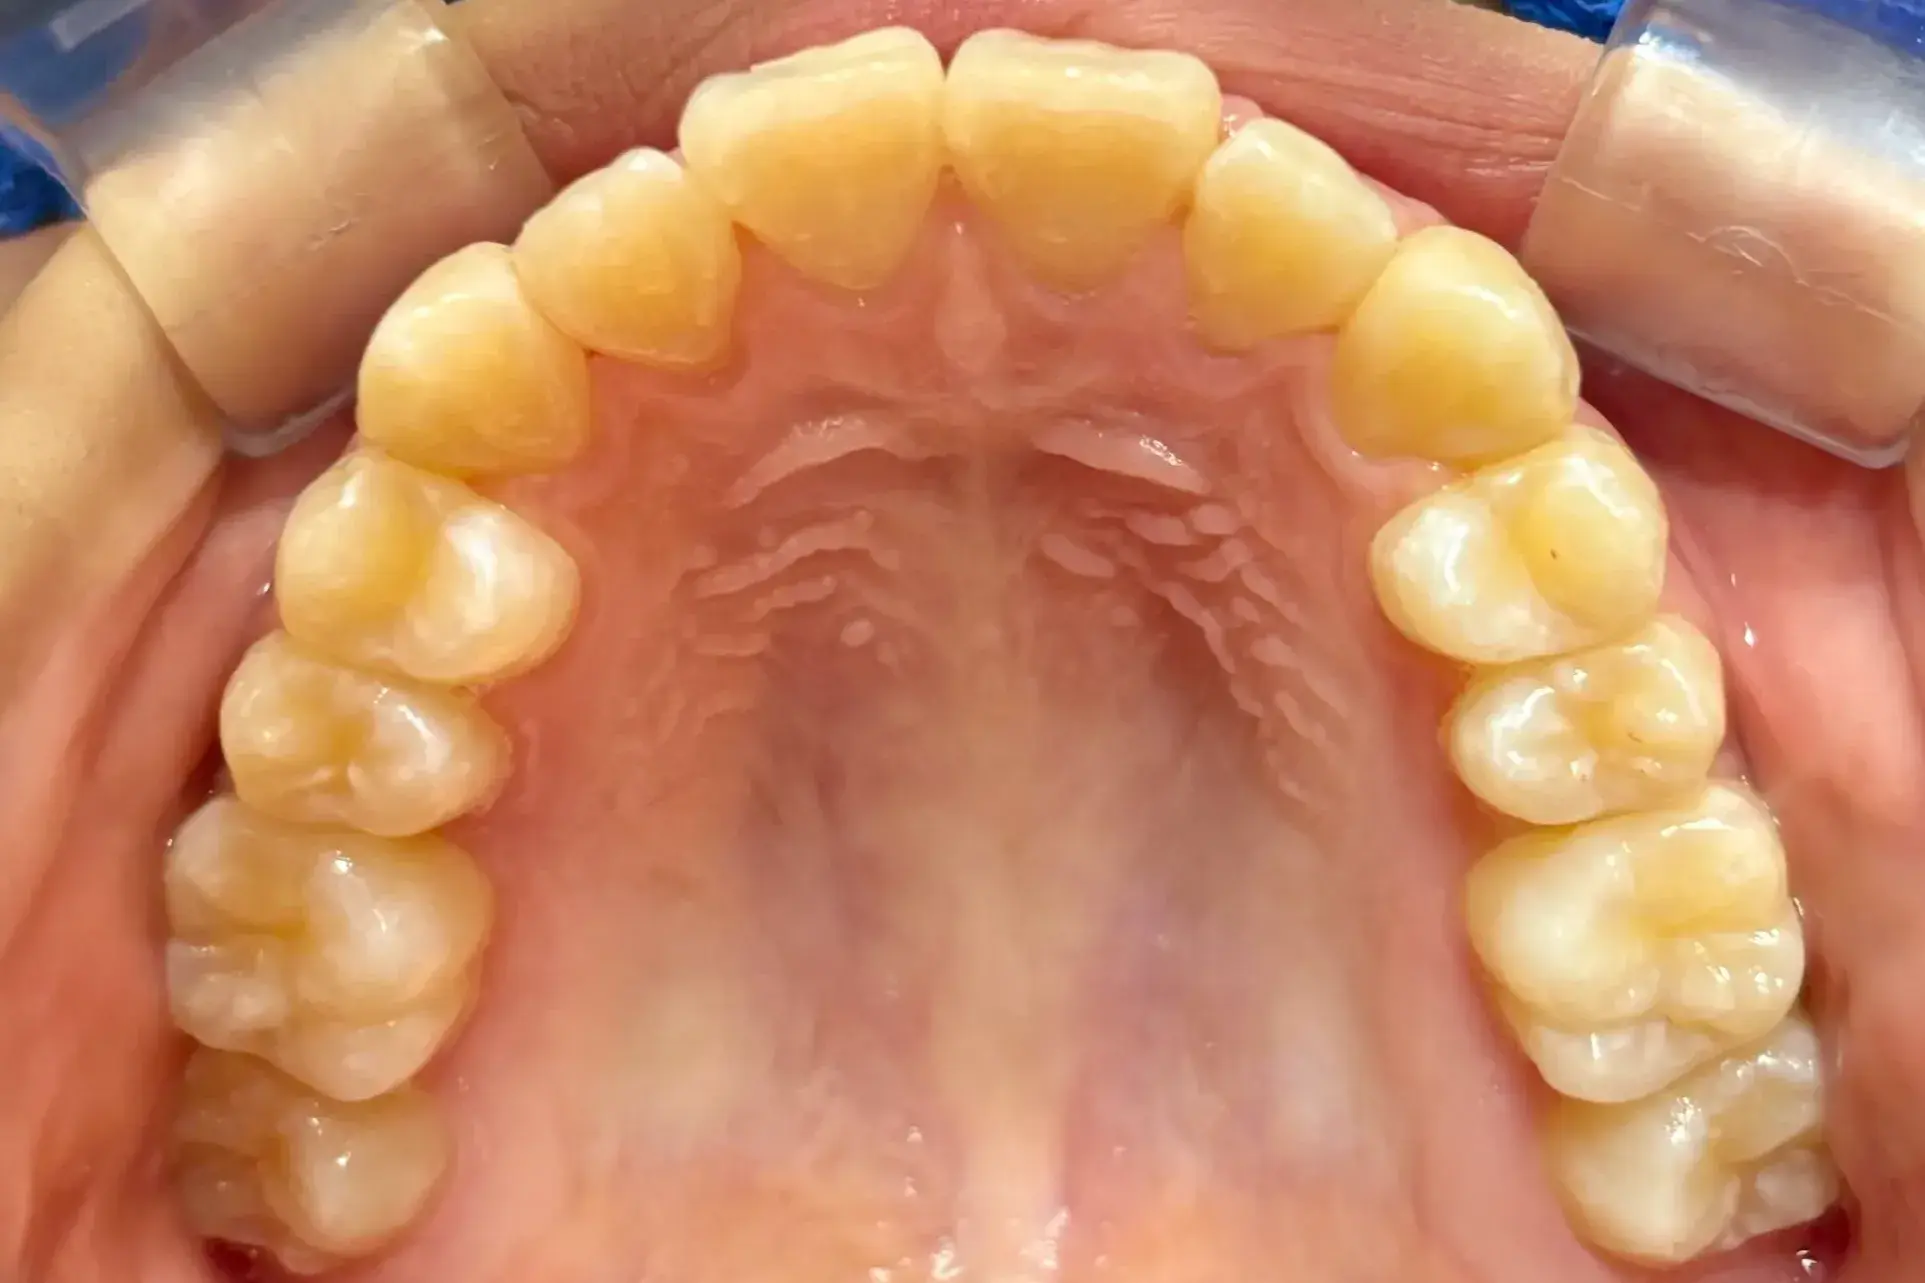

- 症例1

治療期間 4カ月

治療費 23.1万円(月額1,925円~)

※上顎前歯部、下顎前歯部の叢生をマウスピース型矯正装置で改善したケース。矯正治療上のリスクとして、治療中の虫歯、歯根吸収、歯肉炎 ・歯周炎の発生などが考えられる。